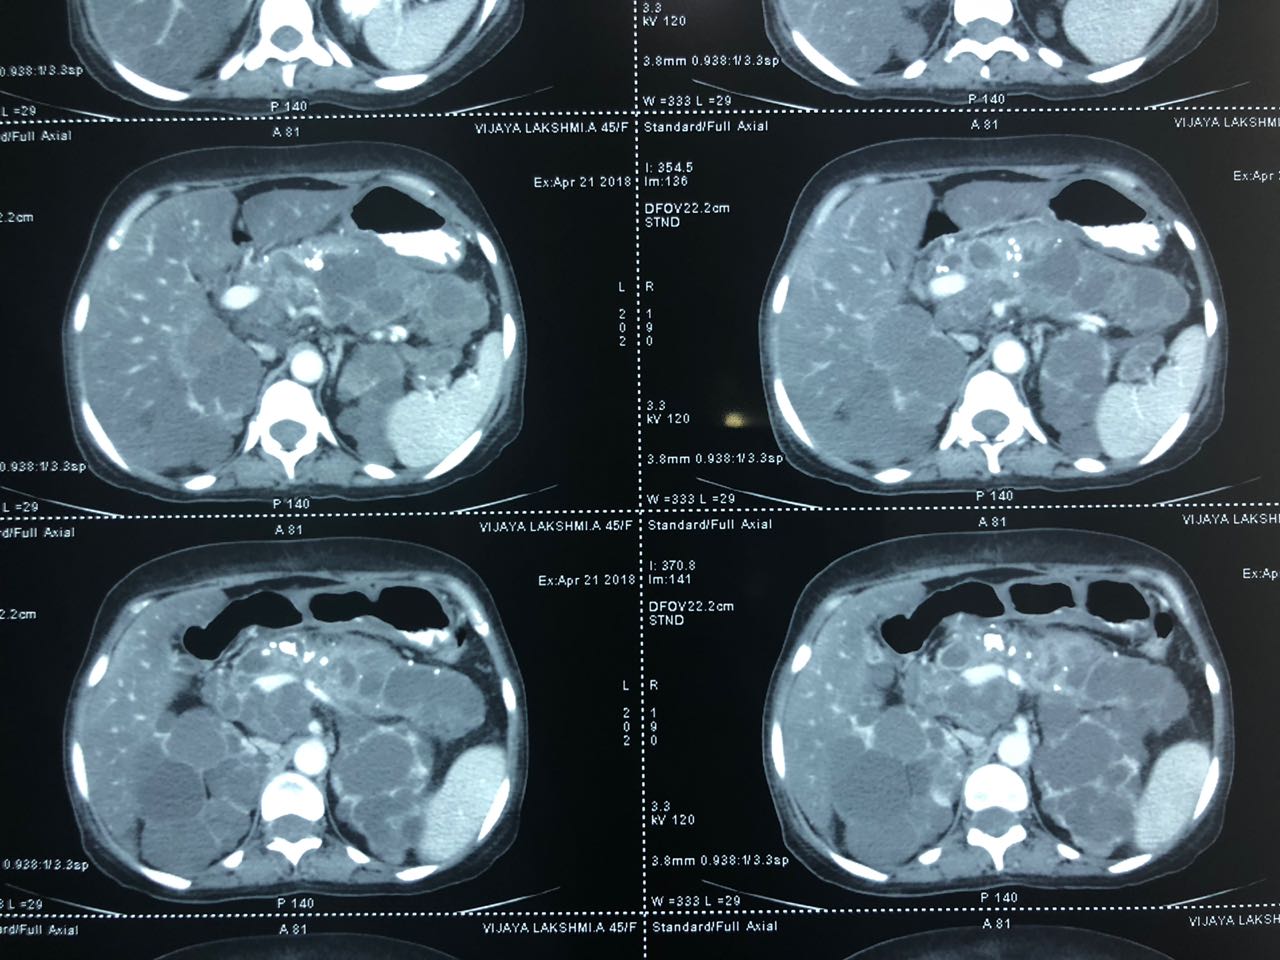

Total pancreaticoduodenectomy with splenectomy done for a 45 yr female with main duct

Total pancreaticoduodenectomy with splenectomy done for a 45 yr female with main duct IPMN with invasive mid-body cancer with bilateral polycystic kidneys. Her EUS, ERCP and fluid cytology , fluid CEA, serum CA19 -9 were all suggestive and a PET showed high uptake in her solid .She is doing well post op but planned for adjuvant CT Rt as had breached capsule and encased splenic vein. Total pancreaticoduodenectomy was frowned upon as a high morbidity surgery due to severe exocrine and endocrine insufficiency with brittle diabetes and ulcerogenicity due to complete loss of pancreatic bicarbonate secretion. But in recent years with easy availability of enzyme supplements, CGM (continuos glucose monitoring devices), insulin pens and long acting PPI the long term QoL of these patients is comparable with partial pancreatectomy patients